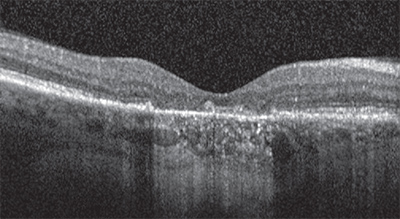

![]() |

Identifying atrophy in the setting of neovascular AMD is at least one step more difficult due to the potential obscuring features of the CNV and associated exudative process. To most precisely study atrophy in this setting and also attempt to isolate the specific impact of anti-VEGF therapy on atrophy, one would focus on atrophic lesions that are separate from and non-adjacent to the CNV lesion. Unfortunately, the challenge to such an approach is that the CNV lesion may grow over time and eventually include the originally non-adjacent areas. Another challenge is that most studies define the CNV lesion based on a fluorescein angiogram (FA), whereas the true/full-extent of the lesion may be found to extend farther when one scrutinizes the optical coherence tomography (OCT) scans of these eyes.